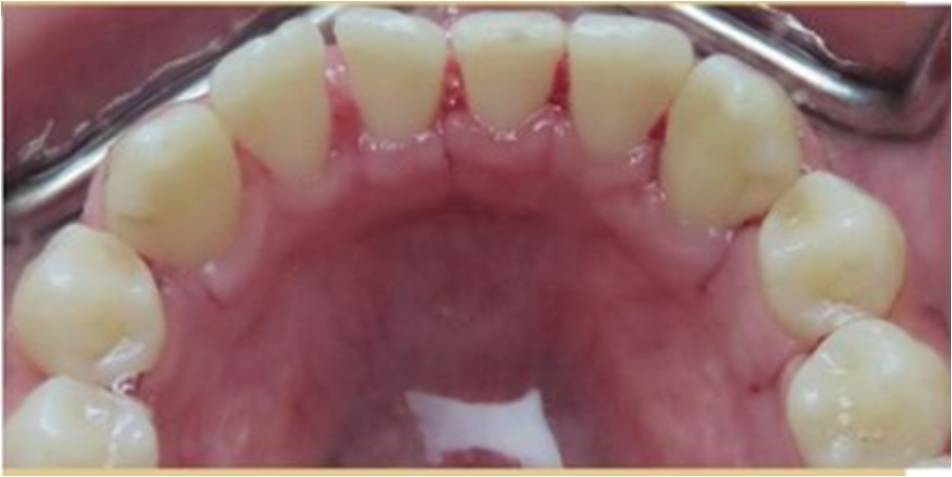

Yes. Even if you’re already very mindful of issues like gingivitis (gum inflammation), you brush and floss twice daily to so there’s no food particles stuck between your teeth, and you use a fluoride mouthwash regularly, you simply can’t carry out a “deep clean” (including below the gumline) like a professional can. The process involves thorough plaque and tartar removal using an instrument called a scaler, followed by treatment with a high-powered electric brush and special toothpaste, and professional flossing to dislodge any hard-to-reach debris and plaque.

Your teeth may, indeed, feel a little looser after having a deep clean, but this is definitely nothing to worry about. When the build-up of plaque and tartar is removed from in between individual teeth, naturally there is a space where it has been accommodated – in some cases, a heavy buildup has been gathering over a long period of time. The feeling of looseness shouldn’t be seen as a problem, however, and while it might take a little getting used to, it’s actually a sign the procedure has been of benefit.